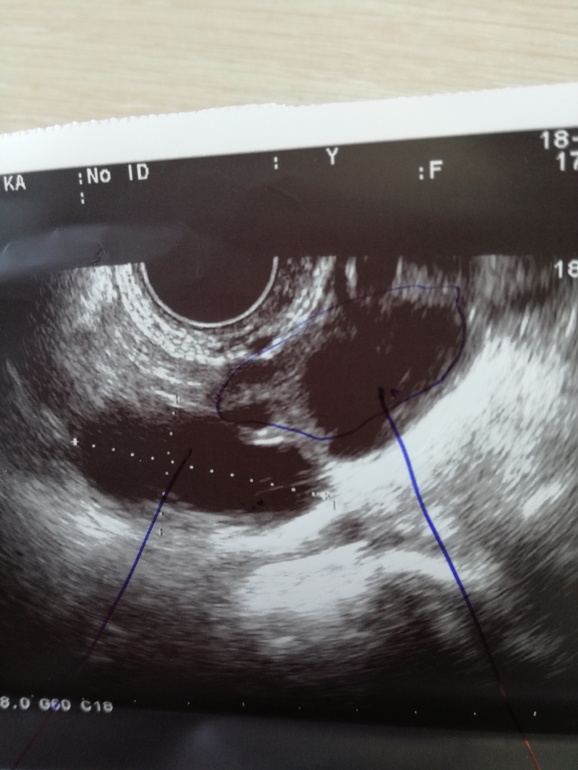

в прошлом цикле был ДФ слева,но не лопнул,а перерос в кисту(около 5см)..была на УЗИ на 10ДЦ сказали киста не ушла((и беременности в этом цикле не ждите...

сходила на узи на 16ДЦ(обычно цикл 32д) к другому узисту и в другое место,сказала что это параовариальная киста и что есть 2 ДФ в каждом яичнике...фото и заключение этого узи прилагаю...

скажите у кого была похожая ситуация??что скажите по снимку??ждать О или она уже была??(узистка кстати сказать точно была О или нет не смогла)...

в позапрошлом цикле не было ничего,в прошлом слева был ДФ,но не лопнул и на 25дц сказали что перешел в фукнциональную кисту,а в этом цикле уже другой узист сказала,что это параовариальная киста..вот как так?!

пя 25мм,а ля 20мм..мне кажется уже наврядли((

в правом уже перерос,а в ЛЯ киста эта(